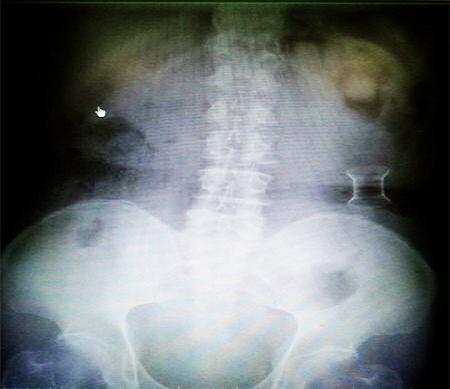

受試患者在結(jié)腸端端吻合術(shù)中,使用我司新研制產(chǎn)品達(dá)到了理想的預(yù)期效果?;颊咝g(shù)后7天、14天X光片顯影,可降解腸道支架均能按研制設(shè)計的預(yù)期時間節(jié)點保持應(yīng)有強(qiáng)度,術(shù)后21天X光片顯示可降解腸道支架已完全破碎,并排出體外。在整個試驗過程中,病患無任何不良反映,耐受良好。